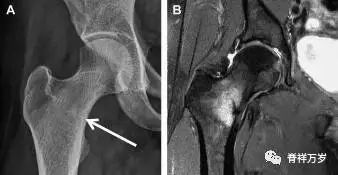

股骨头骨折

股骨头骨折常与髋关节脱位有关。需要注意的是那些既不是因剪力损伤也不是因直接*力暴**作用造成的骨折。这些类型的骨折可能十分轻微。提倡应用 CT 检查,不仅可诊断骨折,而且能评估关节内骨折碎片的位置(图 5)。

图 5 股骨颈骨折伴髋关节脱位。A 股骨头上外侧轮廓缺失(空箭头)注意嵌入上方关节间隙的骨折碎片(黑色箭头)B 冠状位 CT 多维重建(MPR)证实骨软骨碎片(白色箭头)和关节上方的另一个碎片(空箭头)